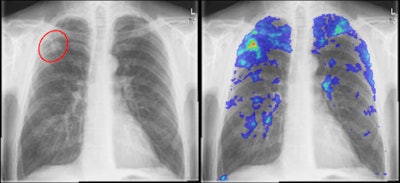

Izquierda: Radiografía de tórax de un paciente con tuberculosis comprobada por cultivo. Se observa una pequeña lesión en el lóbulo superior derecho. Derecha: Resultado de un sistema CAD: Las localizaciones altamente sospechosas están marcadas en rojo, mientras que las áreas menos sospechosas se indican en azul. Todas las imágenes son cortesía del Dr. Laurens Hogeweg.Hogeweg señaló que el interés en la utilización de radiografías de tórax en los algoritmos para exploración de la TB está aumentando; especialmente dado que la radiografía digital suprime muchos de los inconvenientes asociados con los rayos X convencionales, tales como el uso de películas y químicos. Los rayos X digitales proporcionan un examen de la TB rápido y económico, y las investigaciones recientes han demostrado un buen desempeño, dijo.

La curva ROC de este estudio preliminar muestra el potencial para reducir el número de imágenes que deben leerse en un programa de exploración extenso. Esto puede lograrse al eliminar los estudios que el CAD considera normales y manteniendo una alta sensibilidad para casos de TB (indicados por las líneas rojas).Al mirar específicamente el desempeño con un 95% de sensibilidad, el software CAD produce una especificidad del 57%.